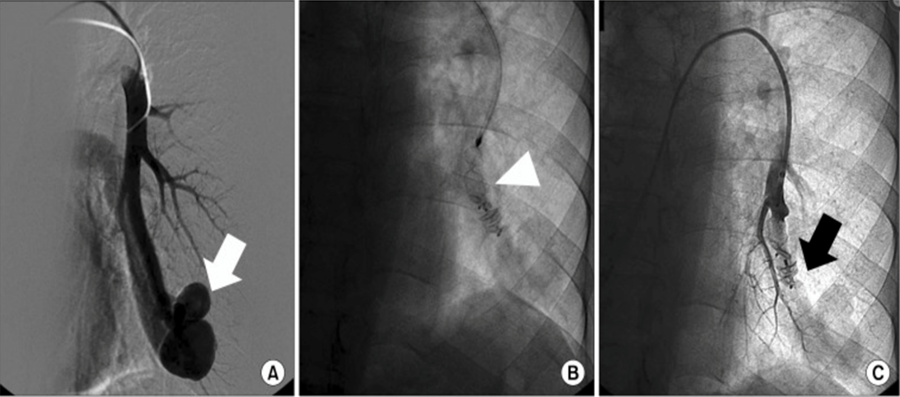

主动脉疾病腔内治疗

对于主动脉疾病的治疗,腔内修复术的应用愈加广泛。与此同时,随着经验的积累,如何减少术后并发症的发生,为患者带来更好的预后,逐渐成为临床医师关注的话题。如:术后内漏都是主动脉疾病腔内治疗后常见的并发症。AVP栓塞效率高、定位精准可充分满足术者对于内漏预防与处理、夹层破口栓塞等治疗需求。

陆清声教授:EVAR术后Ⅱ型内漏预防与主动脉夹层破口治疗新方法

郎德海教授:AVP Ⅱ型栓塞锁骨下动脉应用体会

Amplatzer血管塞病例集锦 — 主动脉疾病

图片

使用AVP2栓塞髂内动脉预防2型内漏

使用4代血管塞进行肠系膜下动脉预栓塞防止2型内漏发生